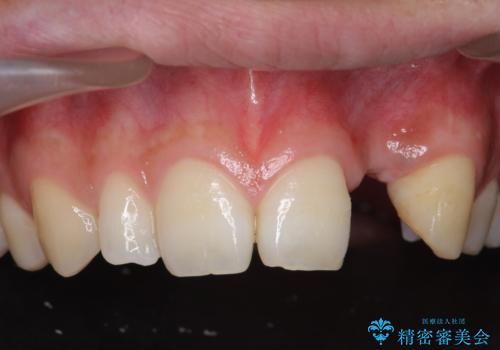

- 前歯の永久歯が元々なく、乳歯を失ったタイミングで前歯の審美性の回復を求めて来院されました。

機能・審美性の回復手段として、インプラント治療・ブリッジ・部分床義歯が考えられます。

それぞれの治療に特徴がありますが、取り外しの必要がなく隣の歯を削る必要も必要ないインプラント治療を選択されました。

前歯部にインプラントを埋入し、きれいに仕上げるためには骨の造成技術や歯肉の厚みを増すような処置を行い、インプラント周囲の環境を整備することが肝要です。